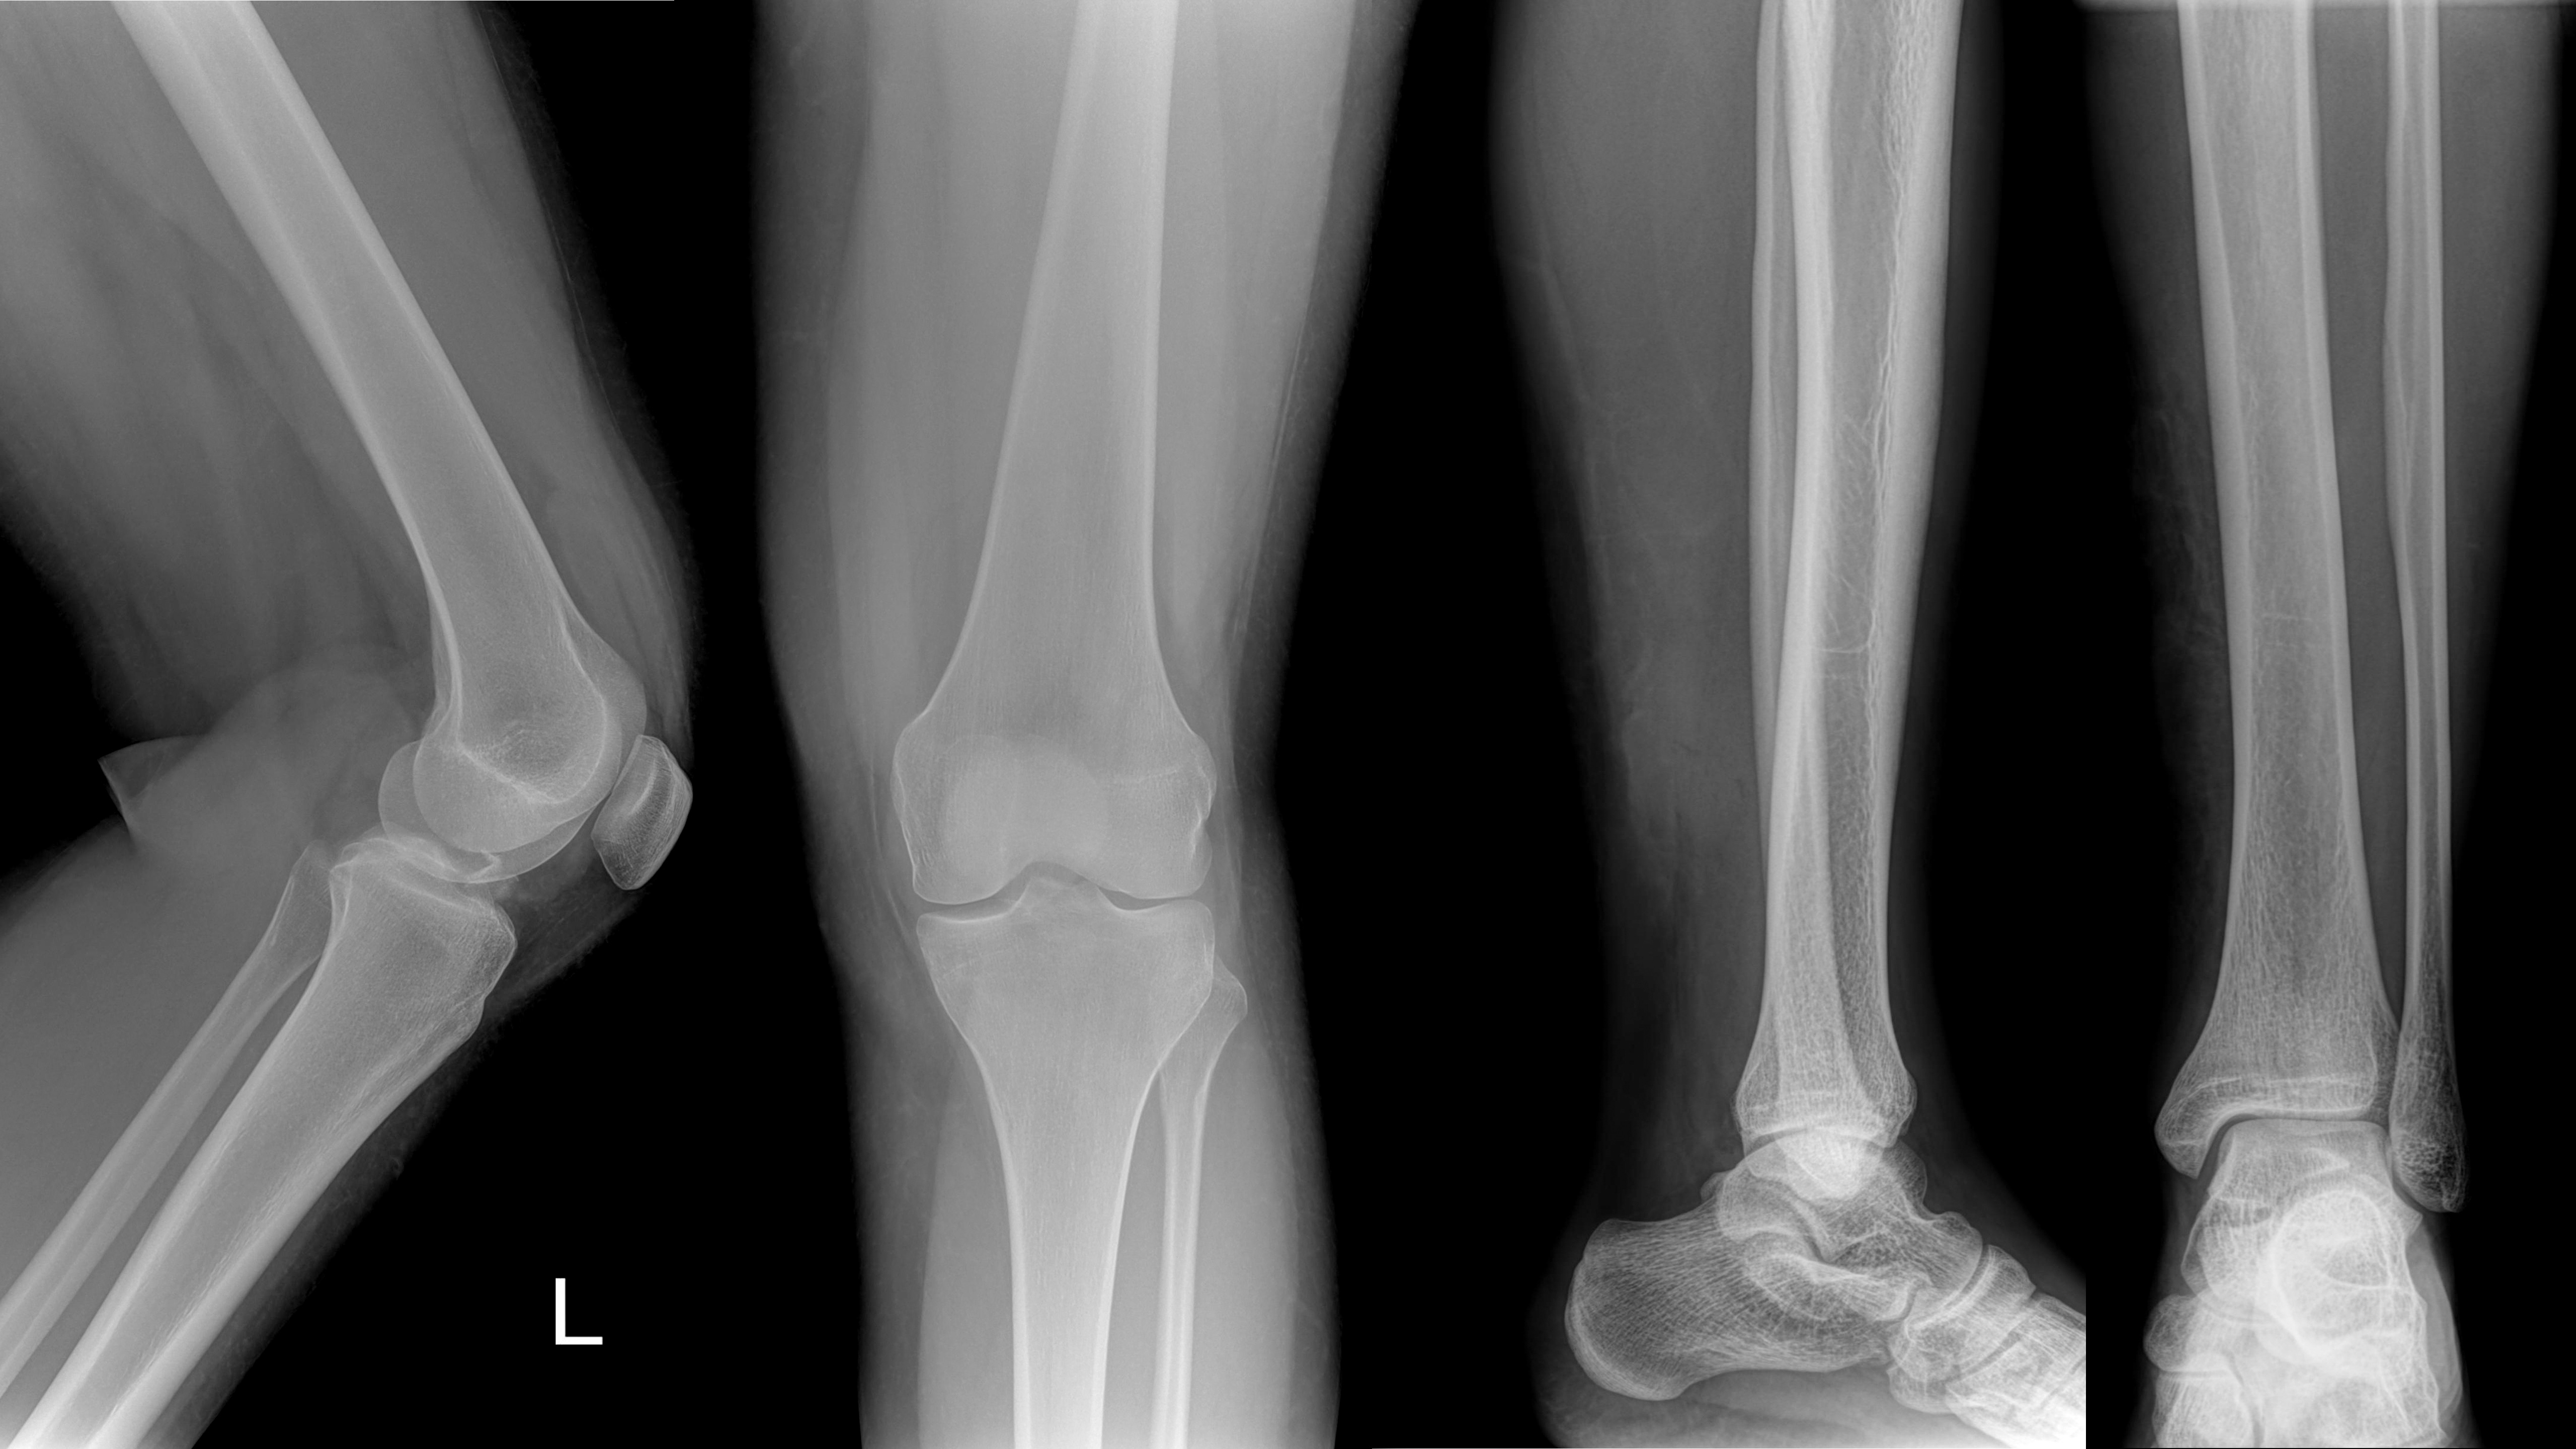

Närbild av röntgenbilder

VI TAR HAND OM DIN KasseradE röntgenfilm

Sitter du på ett gammalt arkiv med röntgenbilder som kostar onödiga pengar i form av hyra och personal? Vi hjälper dig.

GAMLA RÖNTGENBILDER GER VÄRDEFULLA ARKIV

Den väl utbyggda digitaliseringen för framtagning av röntgenbilder inom vården gör att de gamla röntgenarkiven blir mer och mer inaktuella. Silverpriserna täcker oftast kostnader som uppkommer i samband med återvinning och destruktion av filmen - en bra anledning att göra en ordentlig utrensning av röntgenarkivet.

SMIDIG HANTERING MED ATT PLOCKA ISÄR FILM OCH KUVERT

Röntgenfilm som ligger i kuvert har just nu ett silvervärde som redan vid leverans oftast täcker kostnaderna för upparbetning av silvret och plasten. Vi kan separera filmen från kuvert i processen - det betyder att du och dina medarbetare slipper tömma kuverten själva. Lämna allt till oss så löser vi resten. Vi kan även hjälpa till med plockning av filmen i transportboxar om så önskas.

HÖGSTA SEKRETESS

När filmen ligger kvar i kuverten krävs högsta sekretess i samband med utsorteringen så att inga namn eller eventuella journaler kommer i orätta händer. Vi har över 40 års erfarenhet av omhändertagande och återvinning av avfall från röntgenverksamhet. All hantering sker med högt ställda krav på en miljöriktig återvinning och destruktion samt full sekretess genom hela processen.

Kontakta din närmaste anläggning, så hjälper vi dig bli av med det gamla arkivet. Vi hjälper gärna till med råd och anvisningar i samband med utsorteringen.